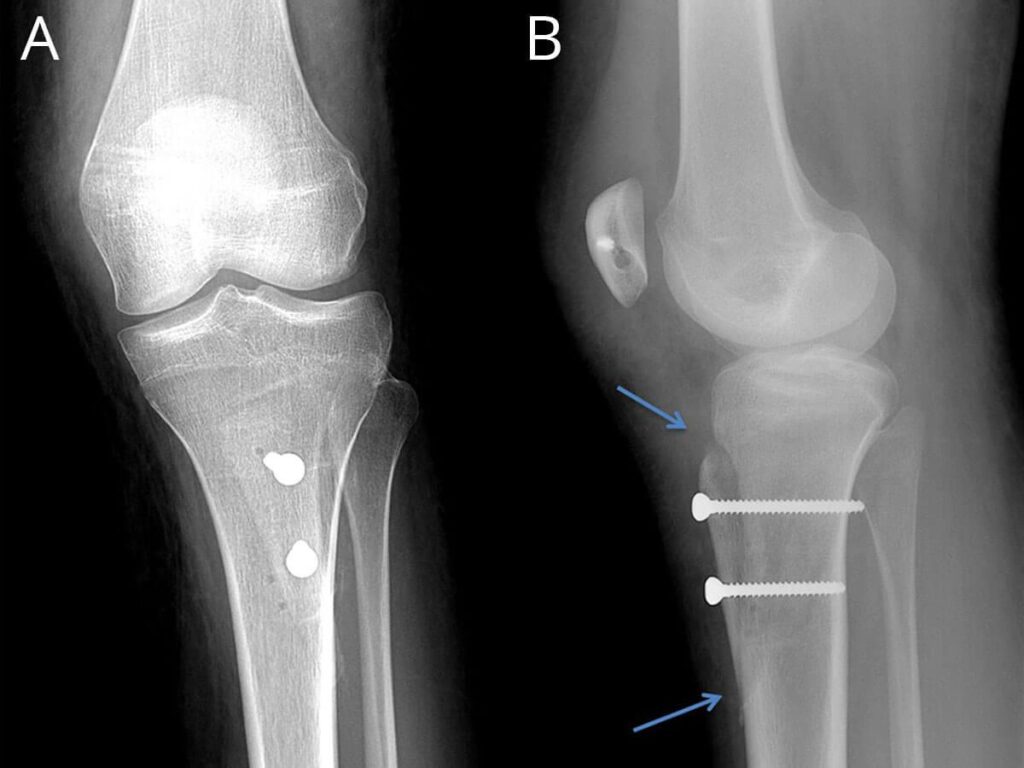

Surgical options range from arthroscopy (key hole) surgery to address tight or loose tissue and possible patella cartilage issues to open reconstruction of ligaments or alteration of the pull of muscles by moving their attachments along with a block of bone and securing this with screws in the same way as a bony fracture is fixed.